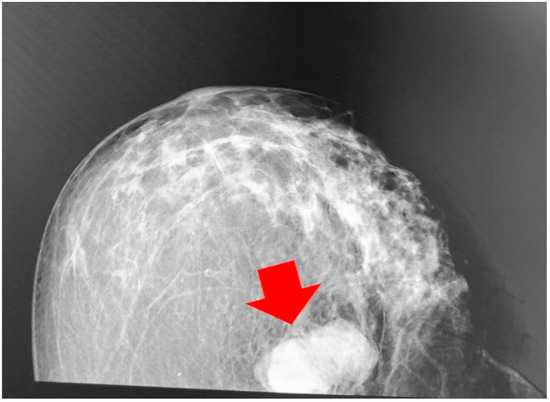

2. A Case Report